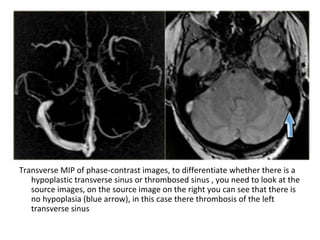

Transverse MIP of phase-contrast images, to differentiate whether there is a

hypoplastic transverse sinus or thrombosed sinus , you need to look at the

source images, on the source image on the right you can see that there is

no hypoplasia (blue arrow), in this case there thrombosis of the left

transverse sinus